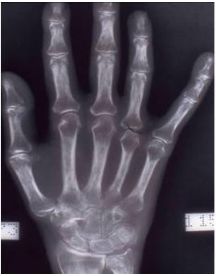

2. 一位43歲女性為B型肝炎帶原者,其主訴為兩側PIP、MCP,及wrist joint腫脹酸痛達兩年之久。但是檢查rheumatoid factors多次均呈陰性反應。手部X-光檢查如圖 。請問要成立rheumatoid arthritis的診斷時,下列何種檢查最為關鍵? (A) ANA (B) CRP (C) Anti-cyclic citrullinated peptide antibody (D) Complement levels (E) Anti-RNP